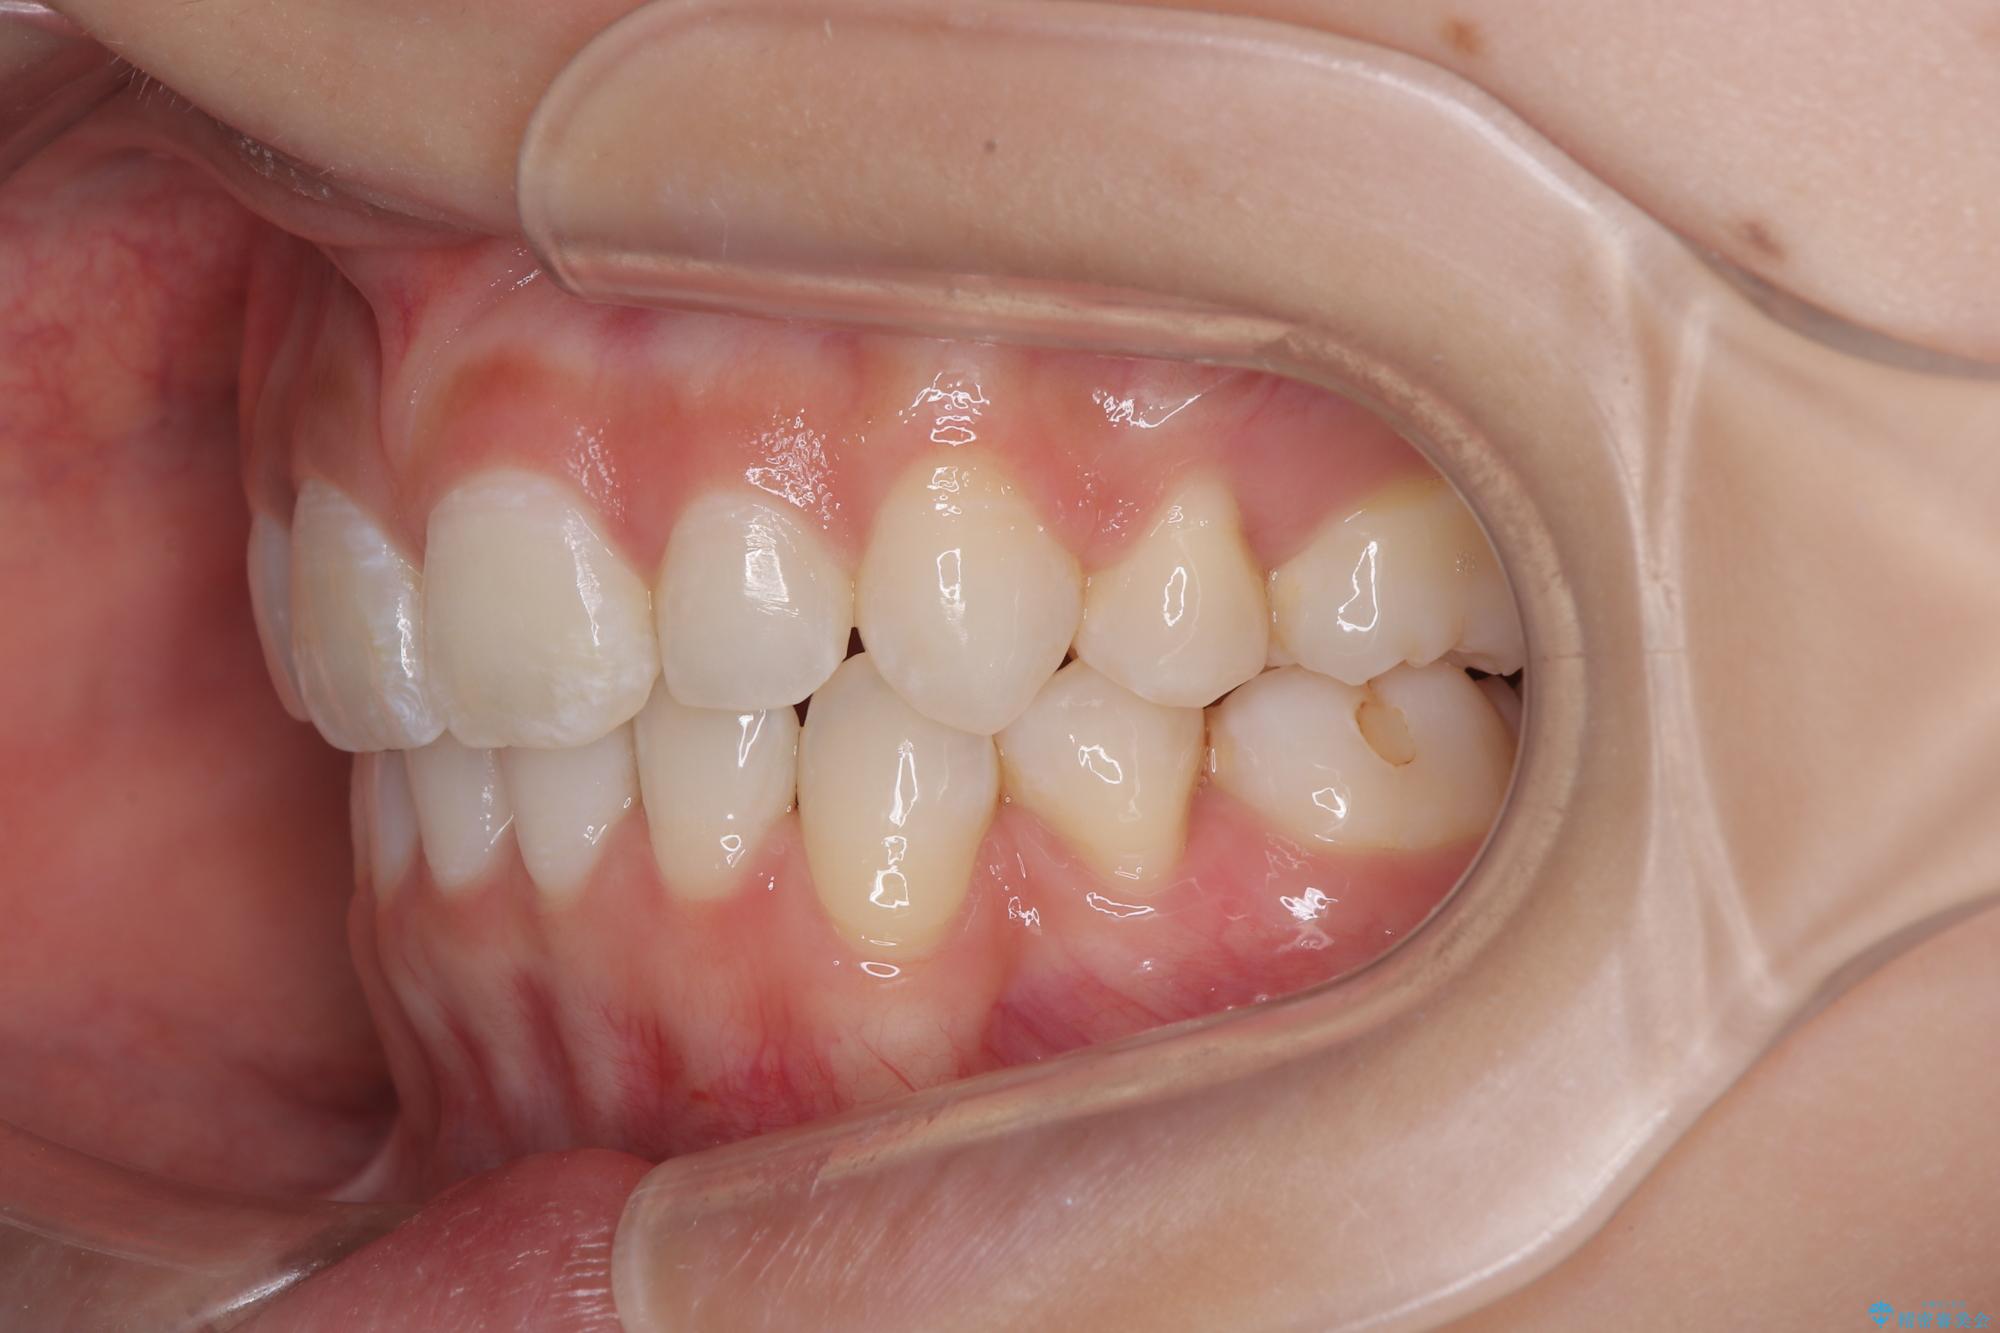

下唇に前歯が当たって跡が残ってしまう状態でしたが、スッキリとした口元に仕上げることができました。